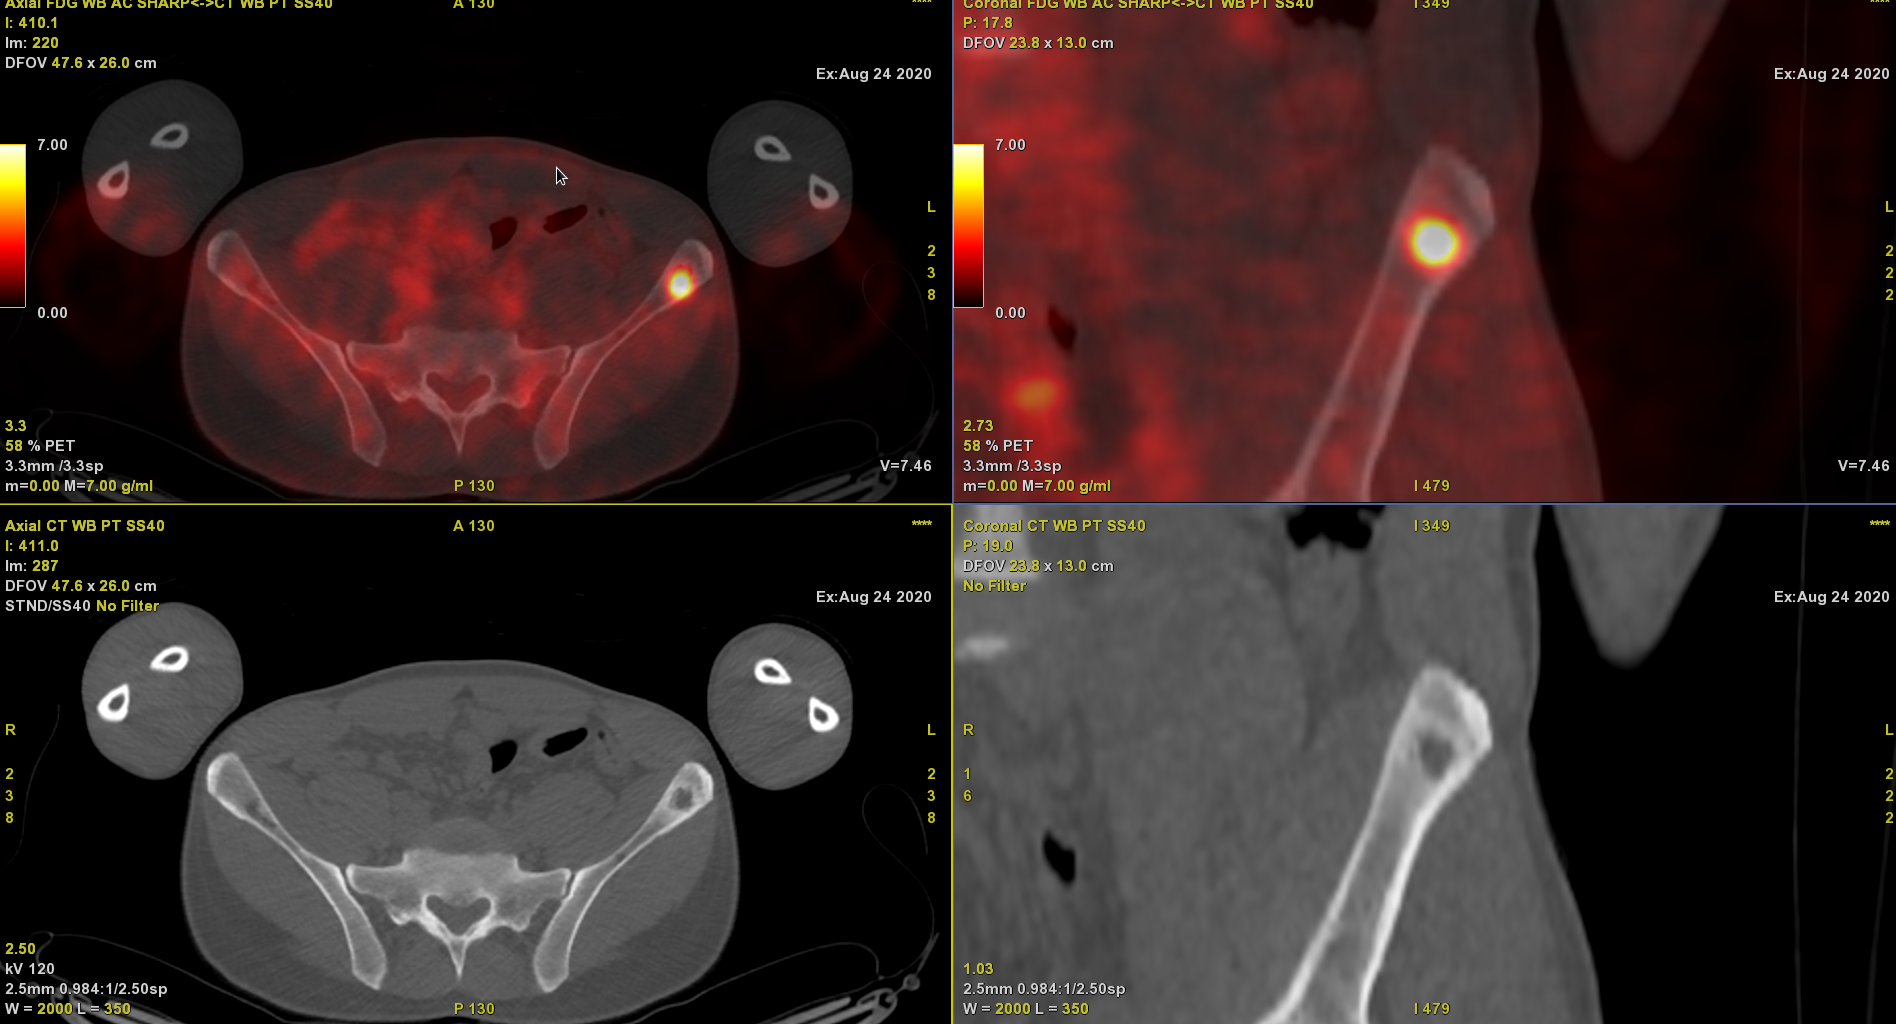

Patient de 38 ans d’origine sénégalaise (résident en Belgique depuis 10 ans) réalisant un TEP/CT 18F-FDG pour mise au point d’une masse de la surrénale gauche et d’une masse de la paroi costale antérieure droite douloureuse à la palpation.

Suspicion d’une néoplasie d’origine indéterminée avec une atteinte métastatique.

Le halo condensant autour de la lésion lytique de l’aile iliaque gauche conforte l’idée d’une lésion lentement évolutive (j’ai déjà vu 2 cas avec une présentation similaire), et donc forcément granulomateuse à cette intensité de fixation !

L’autre hypothèse nettement moins probable étant une tumeur maligne de la surrénale avec métastases osseuses.

Oui en effet il s’agit d’une tuberculose. Le diagnostic a été posé après biopsie de la masse costale droite.